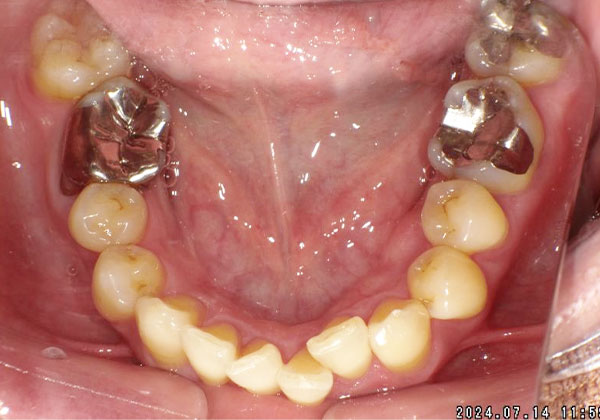

◆マウスピース矯正(50代女性)

(主訴)抜歯をせず歯並びを治したい、矯正中も目立たない方法がよい。

非抜歯で1年弱の治療期間で上下ともに歯列が整った症例です。治療結果だけでなく、費用や治療期間についても想定より安く・短く済み、「治療をもっと早く開始すればよかった」というお声をいただきました。